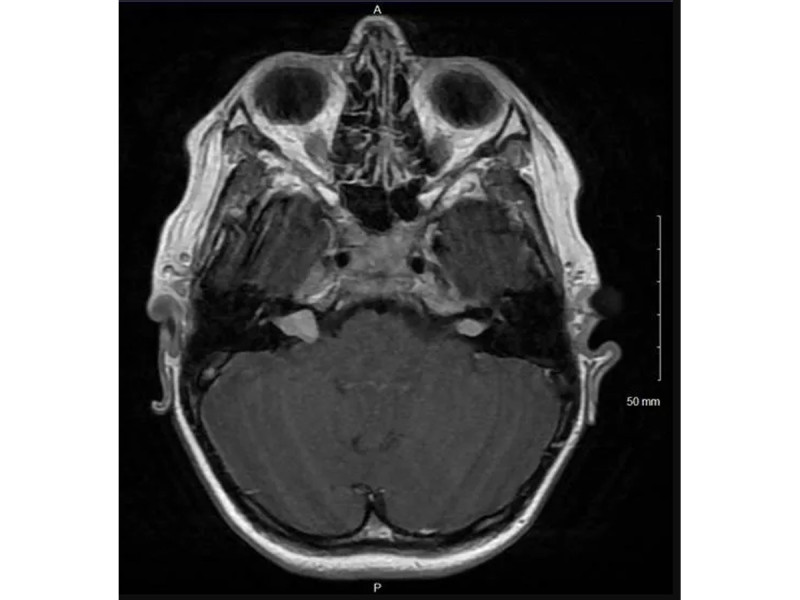

Oscar's scan

Just a bit of context, Oscar has bilateral VS (Vestibular Schwannoma), one of which grew 5mm in 1 year, C2 ependymoma which grew 7mm in 1 year and is turning cystic and a slight hearing loss.

(What is Avastin – see notes below)

Other NF2 related things – T2, L5, S1 schwannomas; parafalcine meningioma; small left cataract; foot drop; left sciatic nerve dysfunction; muscle atrophy – left leg

So our journey into this started in November 2022 when the latest scan showed growth in his Left VS and Ependymoma.